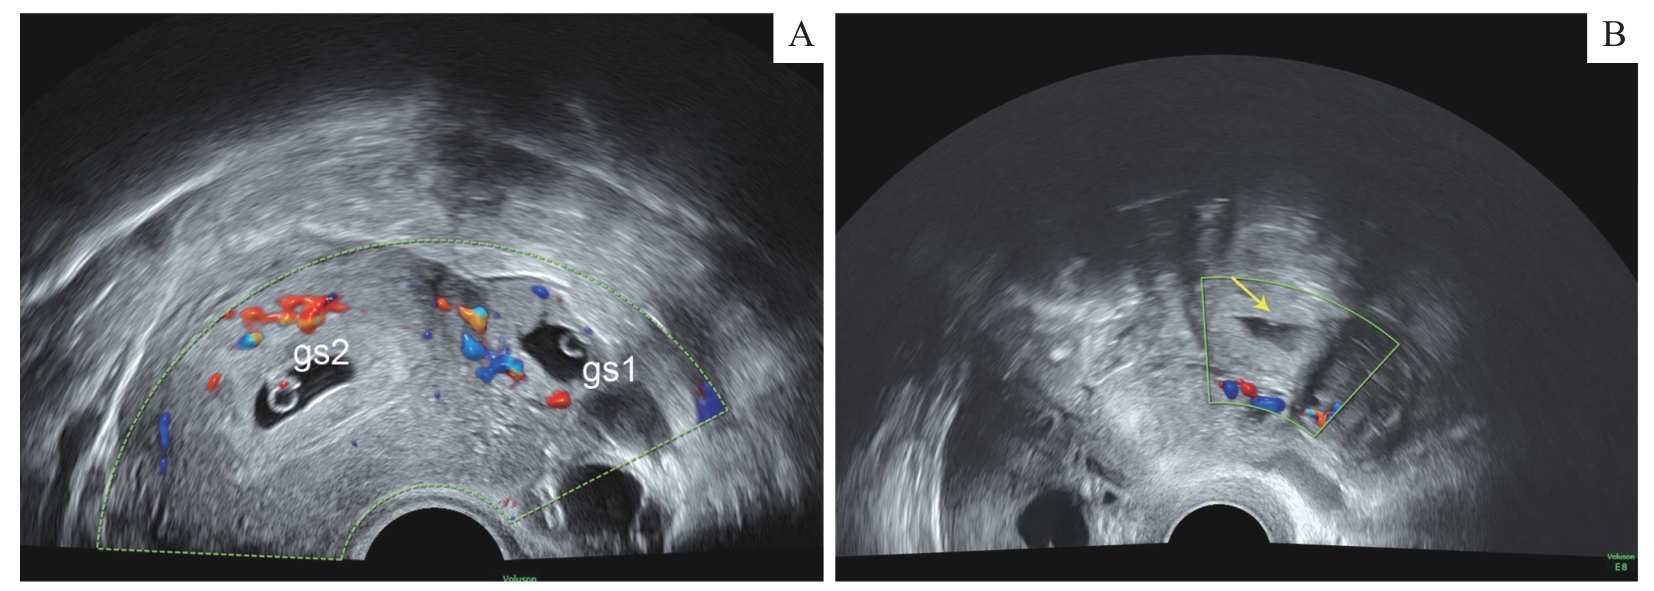

| 图2 超声检查THP代表图像 Note:A. Type Ⅰ (type of gestational sac). B. Type Ⅱ (type of mixed echo). The arrow indicates mixed mass of fallopian tube. gs1—gestational sac in uterus; gs2—gestational sac in fallopian tube. |

| Fig 2 Representative ultrasound images of THP |